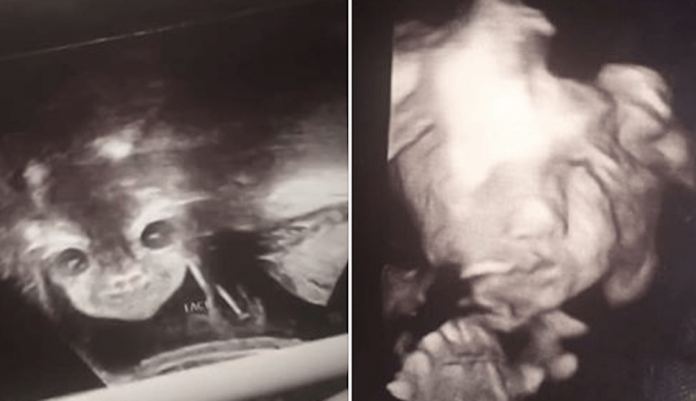

En la ecografía, su hija miraba a la cámara sonriendo de modo extraño y con los ojos bien abiertos.

La perspectiva de esta ecografía es inusual ya que los bebés no suelen colocarse de frente a la cámara durante un ultrasonido.